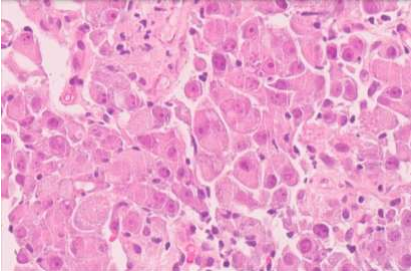

Based on the CT findings, a lung primary was suspected. A lung core tissue biopsy was taken on the 28th of March. It revealed non-small cell lung cancer; most likely a poorly differentiated SQUAMOUS cell carcinoma (SCC). The background stroma was desmoplastic with a near absence of associated chronic inflammation, there was no tumour infiltrating lymphocytes (TILs).

Fig. 3: lung biopsy

Fig.4: lung biopsy

Fig.5: lung biopsy with IHC of p40

It was positive for p40, p63, D2-40 (80%), Calretinin (40%), CK, CK7 and Synaptophysin.

It was negative for TTF1, S100, Melan A, WT1, INSM1, CD56, PSA, NKX3.1, AFP and CD30.  The diffuse strong positivity for p40 made it unlikely to be an adenocarcinoma, since p40 is present in <5% of lung adenocarcinomas and only show a focal expression, if present.